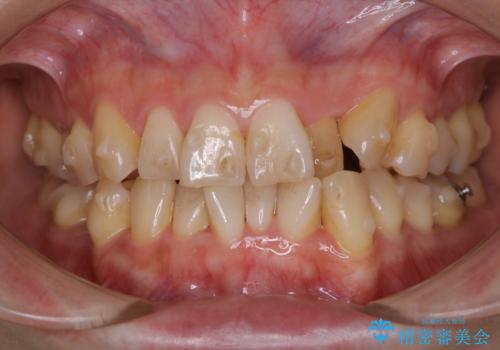

- 忙しくて、しばらくクリーニングをしていないため、全体的にしっかりとクリーニングしてほしいとのことでした。PMTC60分コースを行いました。

プラークが放置されると、そこで病原菌が繁殖し始めます。そうなるとバイオフィルム(歯面に強固に付着したばい菌の膜)になり、歯肉に炎症が生じ歯周病の引き金となります。

プラークやバイオフィルムといった細菌などを放置すると歯石となります。歯石になってしまうと歯磨きでは取り除くことができないため、歯科医院にて専門的な機械や材料を使用してクリーニングを受ける必要があります。

PMTCは審美的な面だけではなく、虫歯や歯周病予防にもなります。虫歯や歯周病予防のためには、お口の中を清潔に保つことが大切です。